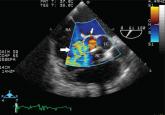

ArticleA continuous cardiac murmurAuthor:Jonathan D. Gardner, MDPublish date: July 1, 2015A 45-year-old woman presents with progressive shortness of breath and a continuous murmur over the entire precordium.Read More